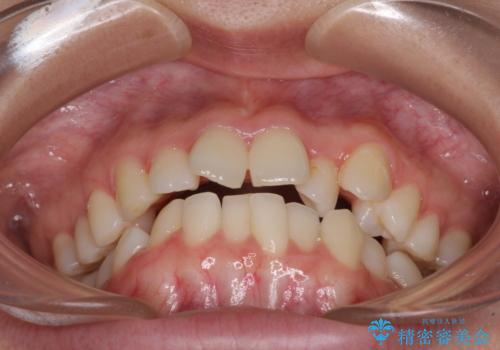

- 前歯のデコボコを気にして来院された患者様です。

前歯のデコボコはもちろん気になるところですが、舌の突出癖により上下の前歯に大きな隙間がある状態でした。

舌の突出癖の影響もあり、非抜歯矯正で治療開始したものの口元が突出し、唇が閉じにくくなってしまったため、途中で第一小臼歯4本を抜歯ししました。